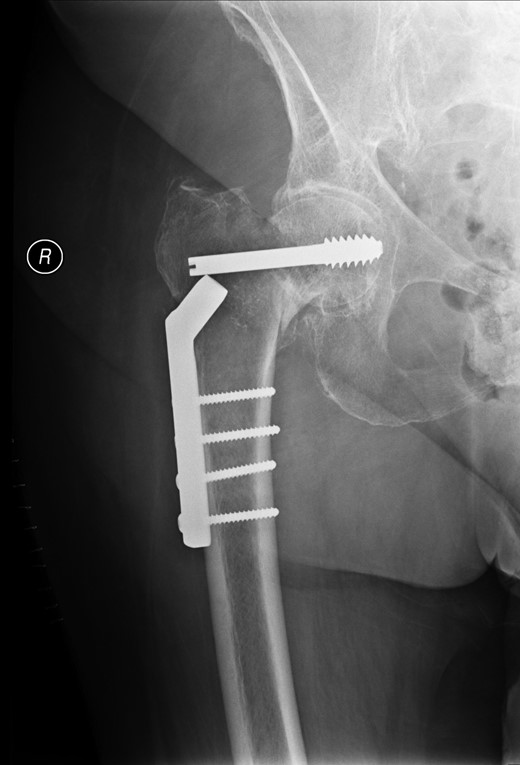

A lady of 88 years old presented with pain in her right hip following a fall at home. Radiographs of the proximal femur revealed an extra-capsular fracture, as shown in Fig. 1. She was taken to the operating theatre within 48 h. In an uncomplicated procedure, the fracture was fixed with a 75-mm, 135°, dynamic hip screw (DHS). A short (25-mm) barrel with four-hole plate was used. Intraoperative screening images are shown in Fig. 2. This position was accepted.